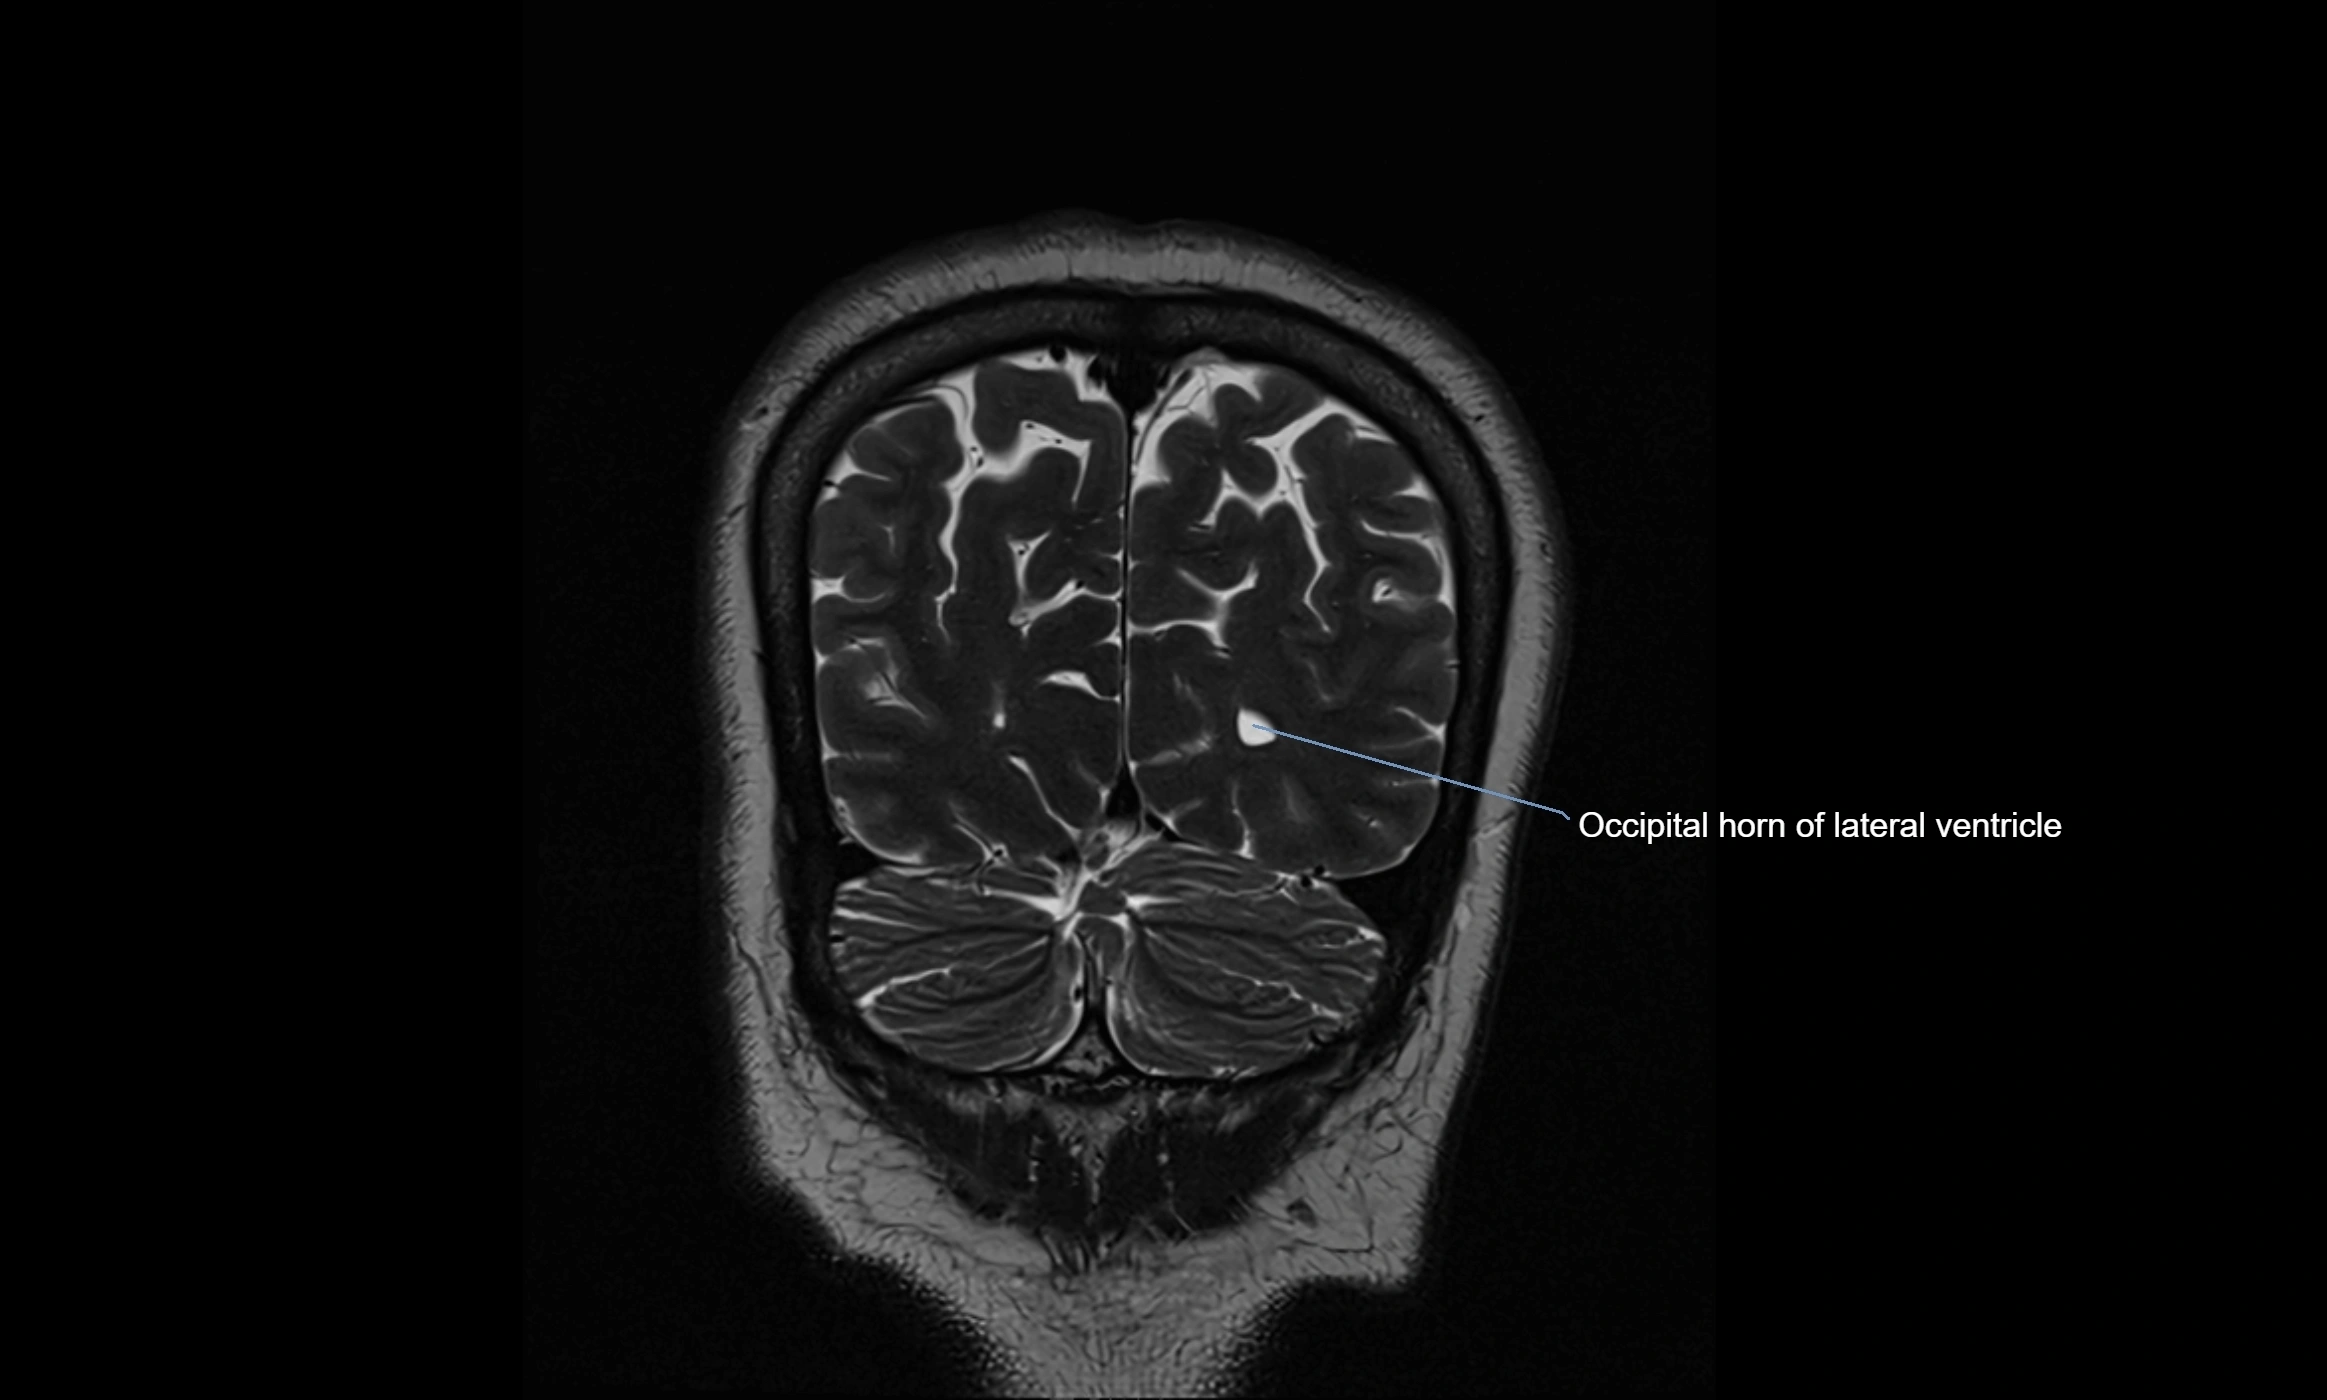

MRI images

image